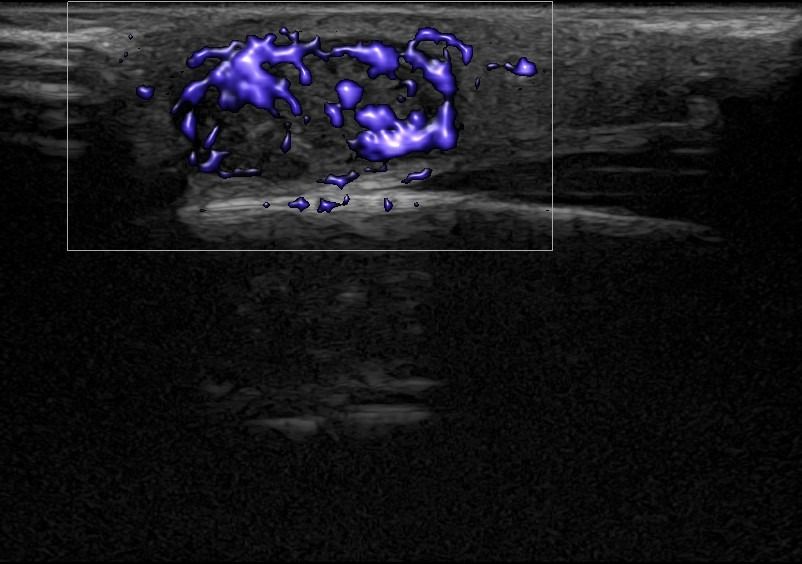

Η τεχνική του Έγχρωμου Doppler μελετάει την αγγείωση της βλάβης. Η τεχνική του Παλμικού Doppler μελετάει την παρουσία αρτηριακών ή φλεβικών στοιχείων εντός της βλάβης. Επίσης πολύ χρήσιμη είναι η Ελαστογραφική Μελέτη η οποία μελετάει τη σκληρότητας της βλάβης. Οι τεχνικές αυτές μας βοηθούν να χαρακτηρίσουμε αν η βλάβη είναι αγγειακού τύπου και αν έχει καλοήθη η ύποπτα χαρακτηριστικά.